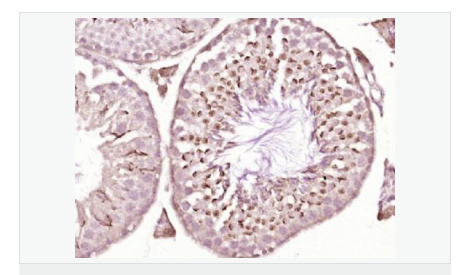

產(chǎn)品應(yīng)用WB=1:500-2000 ELISA=1:5000-10000 IHC-P=1:100-500 IHC-F=1:100-500 Flow-Cyt=1ug/test ICC=1:100-500 IF=1:50-200 (石蠟切片需做抗原修復(fù))